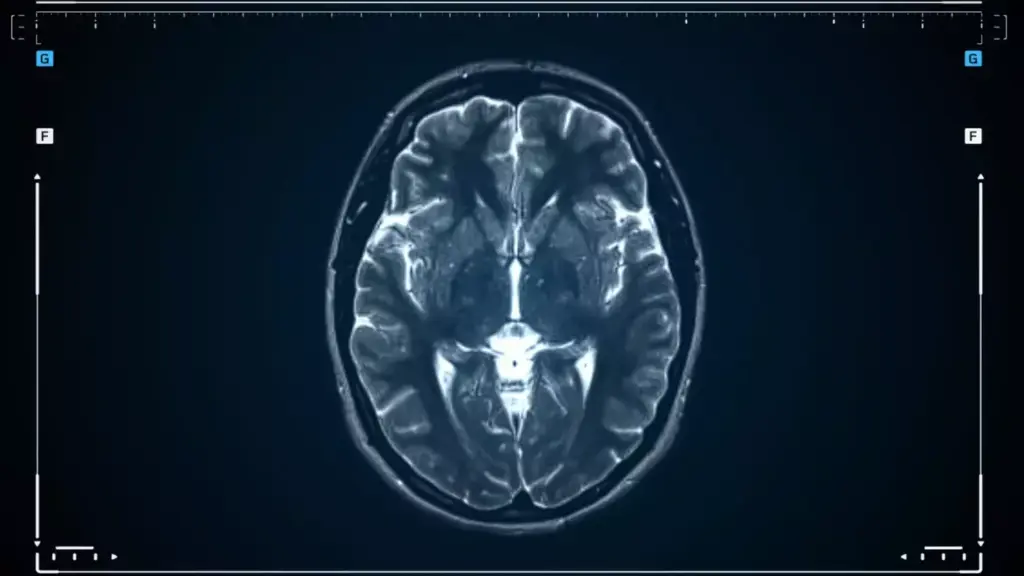

Good monitoring is essential in tracking tumor growth. MRI or CT scans help see how tumors are doing and how well they’re responding to treatment.

Novel Imaging Techniques

New imaging technologies are helping doctors diagnose and plan treatments for brain tumors. Tools like functional MRI and PET scans give detailed info about tumors. This helps doctors choose the best treatment.